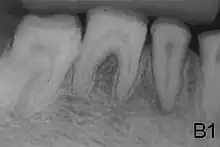

- Enamel of abnormal thickness due to malfunction in enamel matrix formation. Enamel is very thin but hard & translucent, and may have random pits & grooves. Condition is of autosomal dominant, autosomal recessive, or x-linked pattern. Enamel differs in appearance from dentine radiographically as normal functional enamel.[19]

- Enamel has sound thickness, with a pitted appearance. It is less hard compared to normal enamel, and are prone to rapid wear, although not as intense as Type 3 AI. Condition is of autosomal dominant, autosomal recessive, or x-linked pattern. Enamel appears to be comparable to dentine in its radiodensity on radiographs.

- Enamel defect due to malfunction of enamel calcification, therefore enamel is of normal thickness but is extremely brittle, with an opaque/chalky presentation. Teeth are prone to staining and rapid wear, exposing dentine. Condition is of autosomal dominant and autosomal recessive pattern. Enamel appears less radioopaque compared to dentine on radiographs.